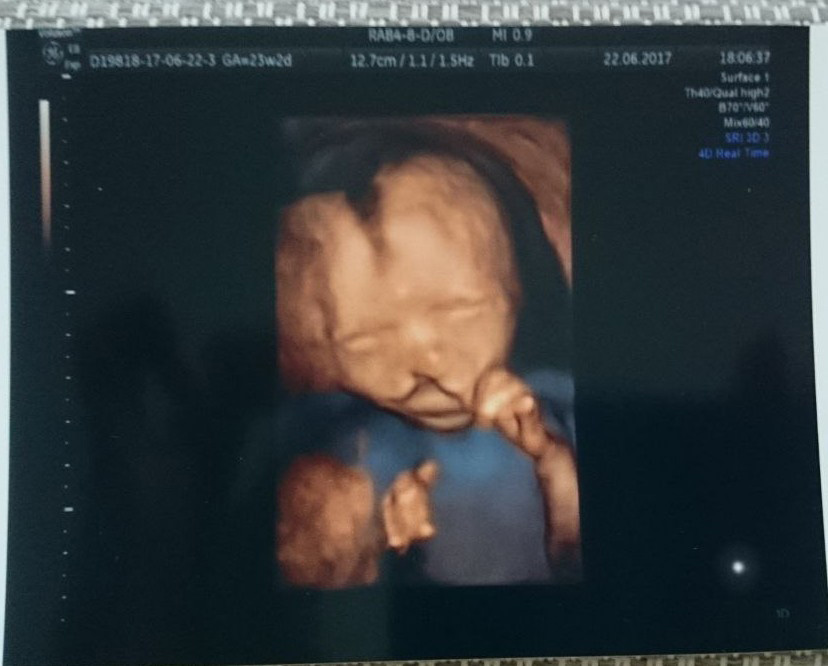

Сразу, конечно, полезла в интернет, увидела все эти фотографии. В тот же день меня направили в Центр планирования семьи. Там был генетик, повторно провели УЗИ, взяли кровь на анализ. Новость о расщелине была не единственной в тот день: добавили под вопросом синдром Дауна. Естественно, генетик предложил сдать амниоцентез, я согласилась.

Результаты амниоцентеза показали, что у нас будет мальчик; синдром Дауна, естественно, сняли. Никаких генетических поломок не обнаружили. Сейчас уже думаю, что его заподозрили из-за маленькой носовой косточки и поплывшего из-за расщелины носа. Плюс я сдавала кровь в сильнейшем стрессе после этих диагнозов.